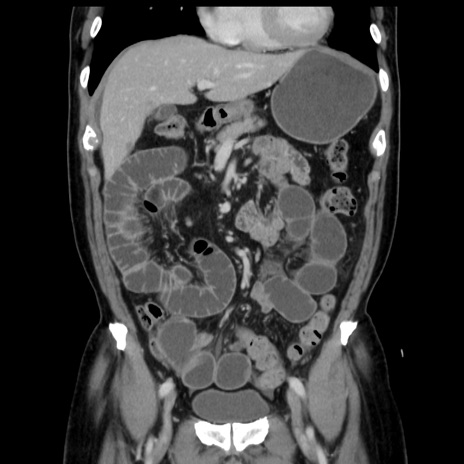

症例16(冠状断像)

【症例】 70歳代男性

【主訴】 腹痛、嘔吐

【現病歴】 約1ヶ月前より間欠的に腹痛と嘔吐あり、当院消化器内科を受診したところCTで多発する肝臓のLDAを指摘され、精査中であった。以降は消化器症状は安定していたが、2日前より嘔気と腹痛があり、同日より排便・排ガスが消失した。改善認めず、 本日、救急外来を受診した。

【既往歴】 大腸ポリープ切除後。

【身体所見】意識清明・会話良好、BT 36.3℃、BP 127/80mmHg、 P 80bpm、腹部:膨満あり、平坦・軟、上腹部正中および下腹部正中に圧痛あり、反跳痛なし、筋性防御なし。

【データ】WBC 7200、CRP 0.77